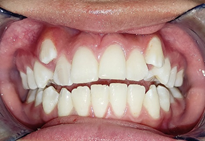

Se prescribió un nuevo examen tomográfico en el que se pudo constatar que se cumplió el objetivo de tratamiento, ya que se consiguió la descompresión de la zona retrodiscal dando lugar a la formación de un pseudodisco que compensó el adelantamiento discal bilateral existente.

Se pudo observar en la imagen tomográfica (Figura 4) la ATM derecha la neoformación de tejido óseo con una ligera erosión en la zona anterior del cóndilo mandibular (A), mientras que en la ATM izquierda se visualizó la formación de un osteofito el cual se genera en etapas avanzadas durante un cambio degenerativo a más de la formación de tejido óseo (B).

Con el presente caso clínico se concluye que, si es posible conseguir mediante la descomprensión en la zona retrodiscal la neo formación de tejido estimulando una fibrosis y por consiguiente a un pseudo disco, también que un factor clave del éxito terapéutico reside en la educación del paciente y sus familiares orientándolos sobre la condición que adolece.